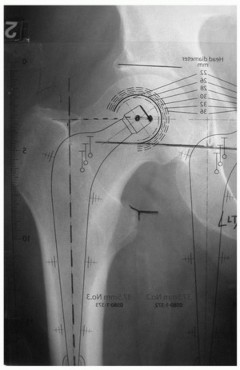

Principles, Planning, and Decision Making Revision total hip arthroplasty is complex and demanding. The stake…

Total Hip Arthroplasty in Patients with Proximal Femoral Deformity INTRODUCTION Proximal femoral deformity in…